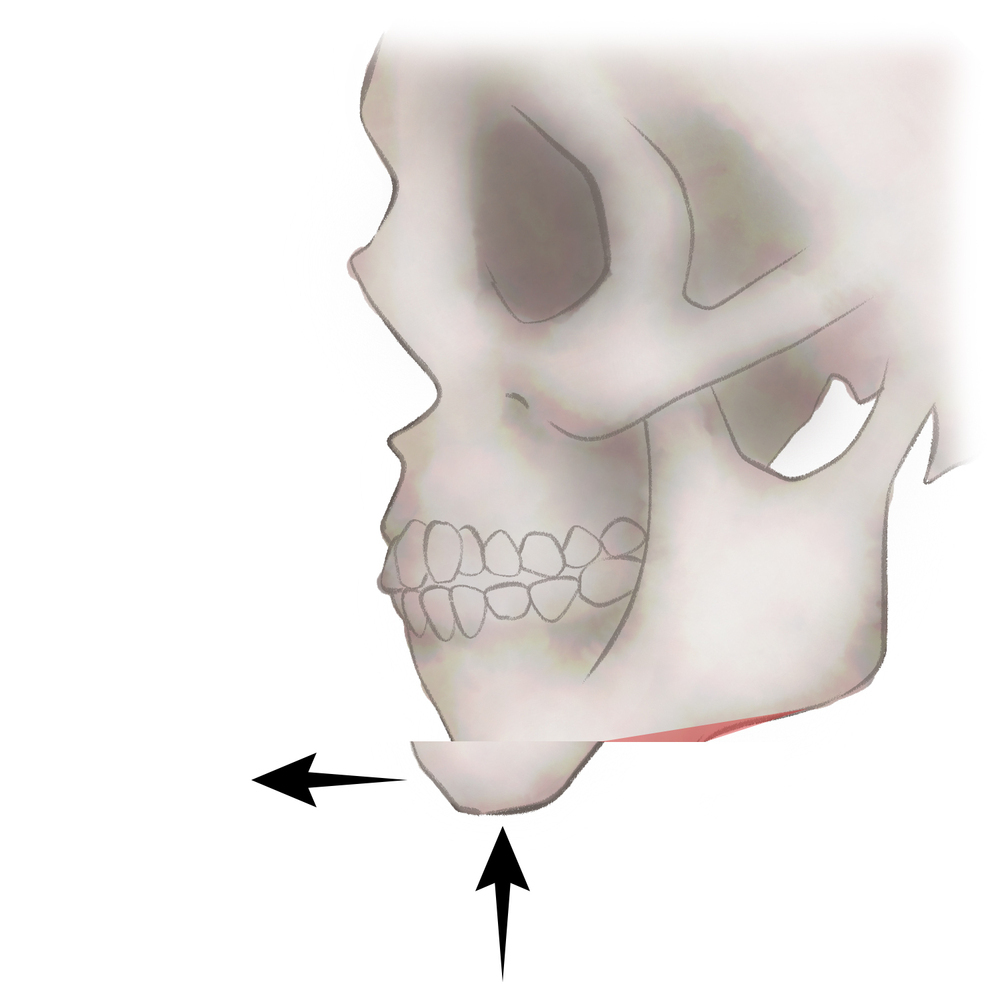

オトガイ骨切り(中抜き)+前方移動

1.切開線をデザインします

2.骨を切り離す、もしくは取り除きます

3.骨を移動させ段差を削ります

4.プレートで固定します